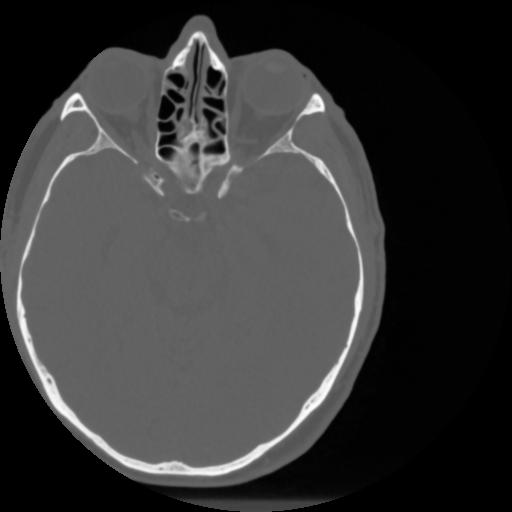

4 CEREBRO,,Vol,0.5,CEREBRO,,